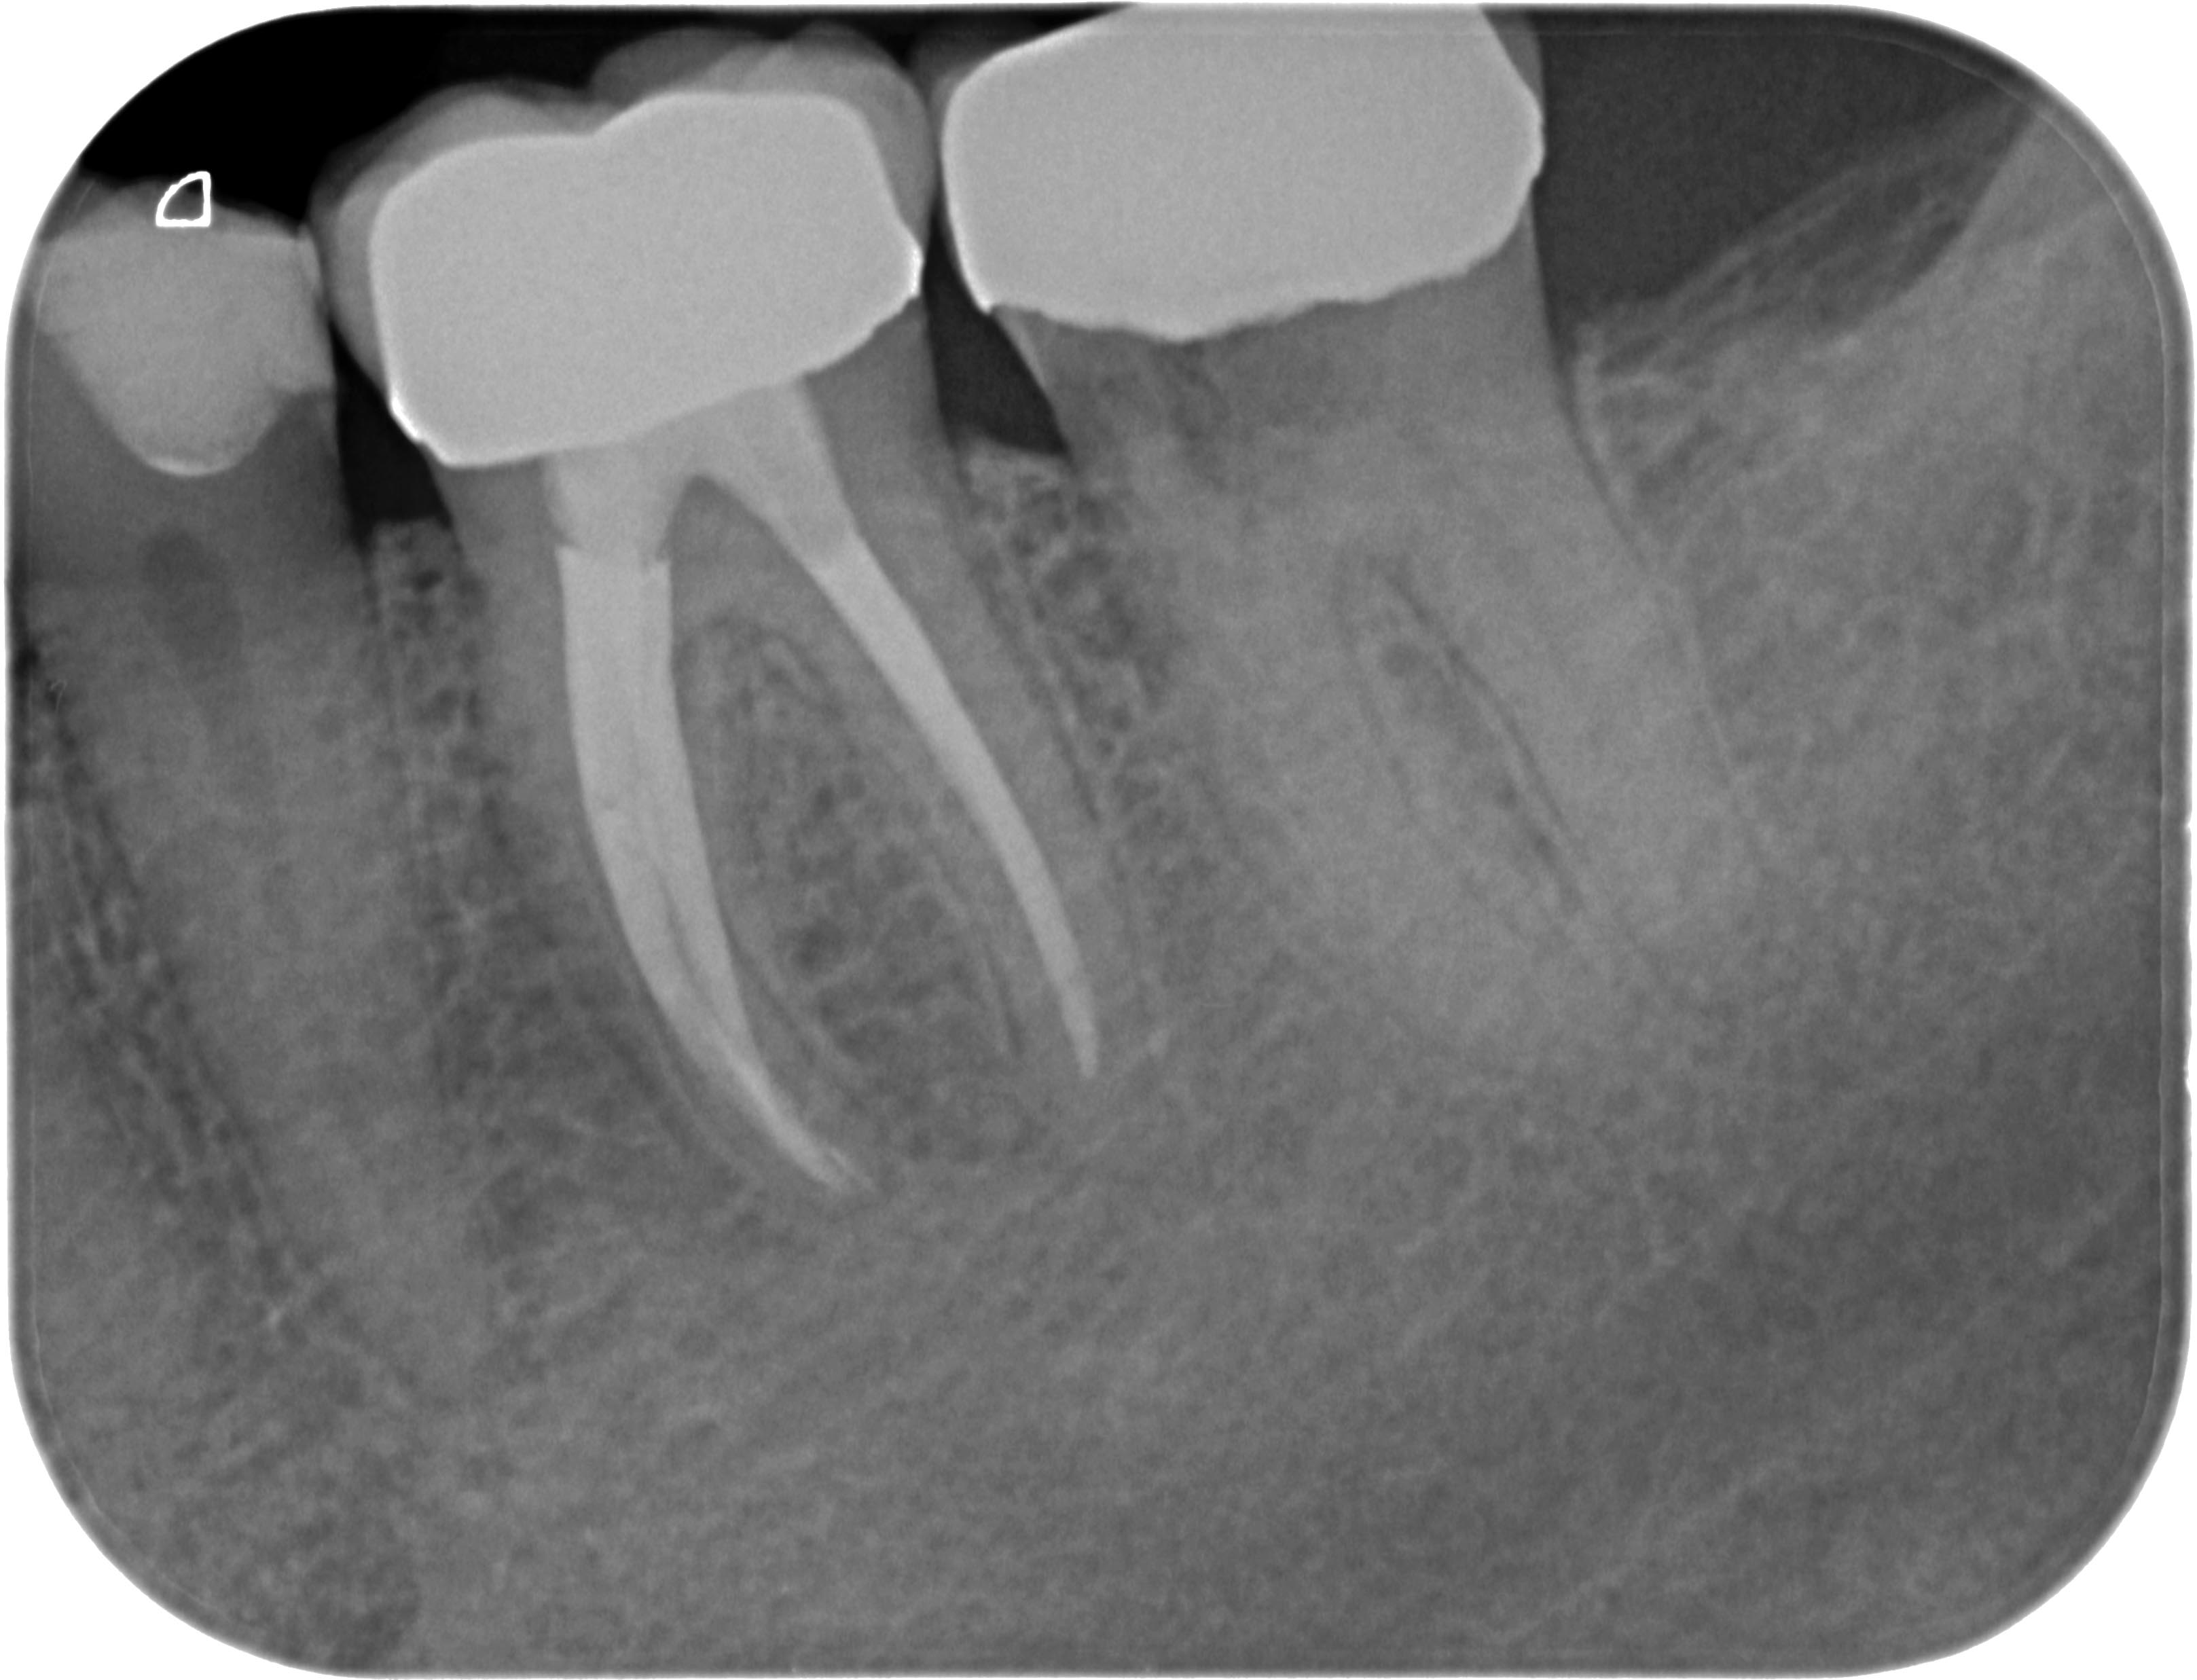

Resorption-1-7 Veröffentlicht 10. Juni 2013 am 3235 × 2474 in Was zeigt das DVT (4) ? Die Fälle Zahn 36, 37